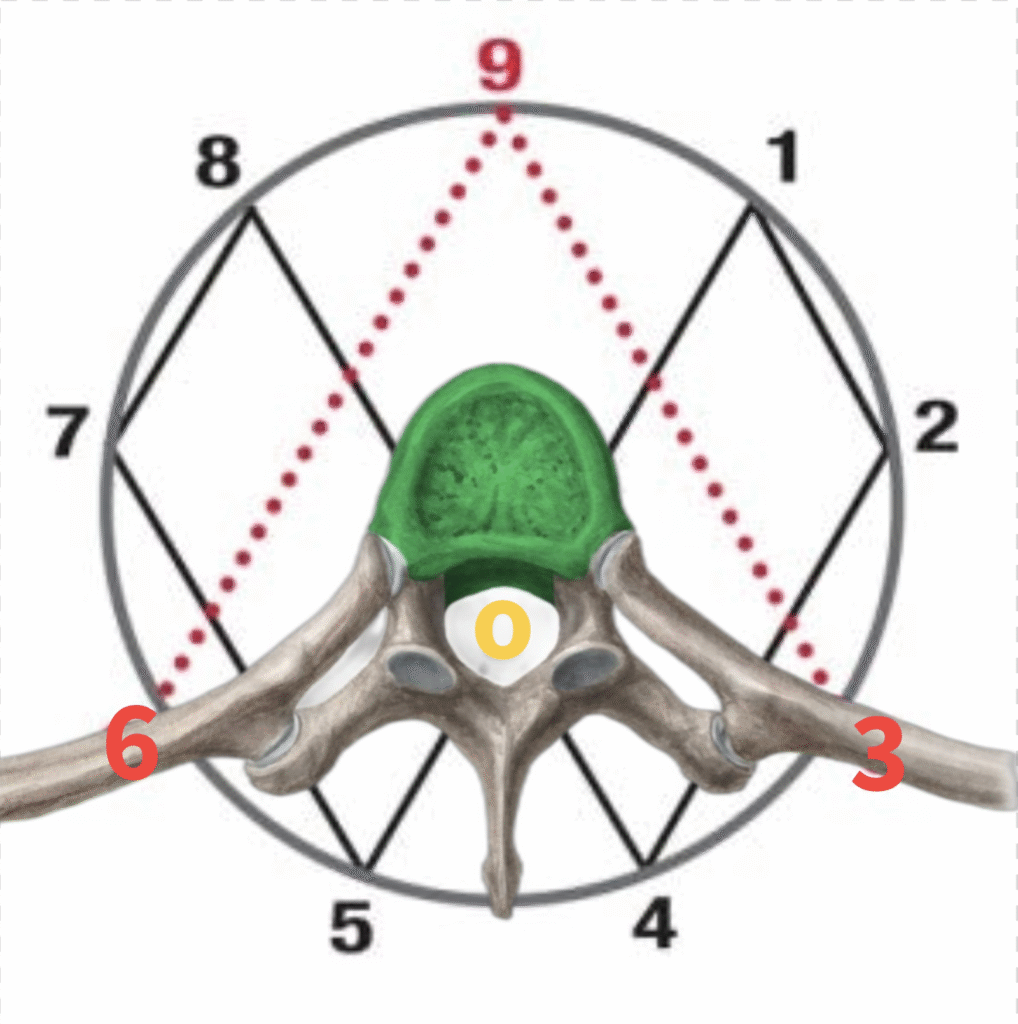

The Thumb Test: Locating Pressure Distortion

The thumb test is not identifying what you have been taught—it is locating:

Zones of overpressurization

Areas where biofluids and tissues have deviated from their natural pathways

Points of stagnation and force accumulation

In these regions:

Fluid motion is disrupted

Pressure builds unevenly

Both high-pressure compression zones and low-pressure collapse zones develop

And critically:

The bodies structure—especially the spine—follows these pressure deviations, not the other way around.

Each body expresses this differently, depending on its unique pressure distribution.

In Hydro Structural diagnostics, this is precisely where the thumb test identifies dysfunction. The thumb locates the point of impact, where:

Pressure has accumulated

Flow has been disrupted

Bio-hydraulic forces are concentrated

This point reflects a localized pressure gradient where fluid is no longer moving efficiently from high-pressure to low-pressure zones.

Nociceptive Response at the Impact Zone

At the stagnation point—where pressure and bio-hydraulic force are highest—even a light touch can trigger a strong nociceptive response.

This occurs because:

The area is under extreme static pressure

Compression and shear forces sensitize tissues

Receptors become highly reactive

In Hydro Structural assessment:

Light contact at these zones produces a noticeable response

This may alter head position or level, reflecting system-wide imbalance

In contrast:

Areas with normal pressure distribution show neutral or minimal response

These regions remain balanced and stable